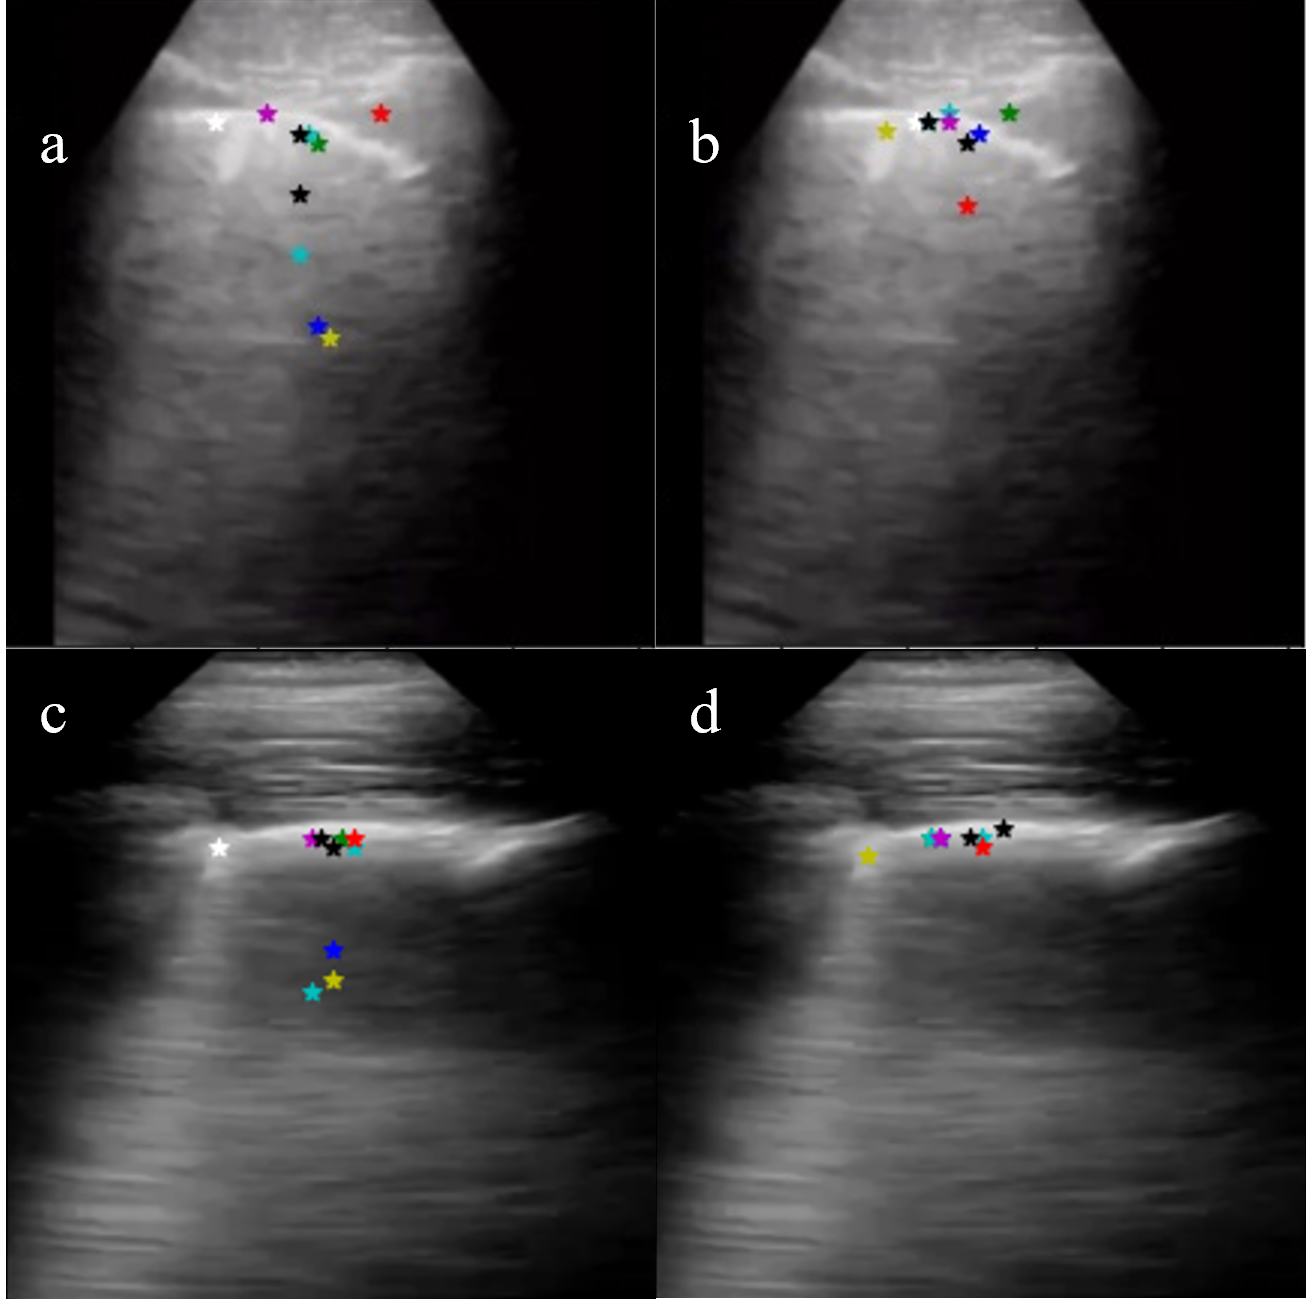

As shown in Fig. 4 application of DGA gave a more stable distribution of key points. With DGA more points were identified on echogenic structures like the pleura.

Refer to caption

Figure 4: (a, c) Without DGA, (b, d) With DGA. The results are far more stable in terms of pleural tracking in cases with bright B patches with the introduction of DGA.